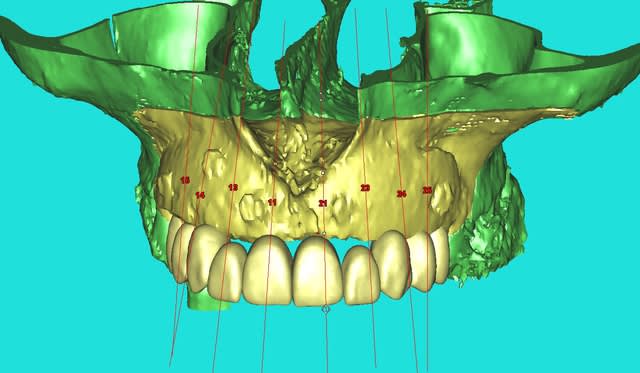

Cross section dhvkc8 - Eugenol

3d dt3qom - Eugenol

Overview uqcp6u - Eugenol